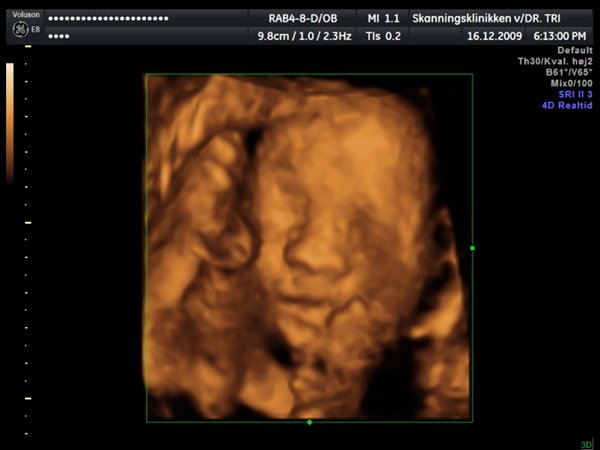

Ja, så var vi til 3D scanning med Ida igår. Og hvad kan jeg sige andet end hun er en meget træt pige

Jeg tror vi talte hun gabte mellem 10 og 11 gange under hele scanningen. Derudover havde hun meget travl med at gemme sig bag sine hænder som hun hele tiden åbnede og lukkede så det så ud som om hun vinkede

Billederne blev ikke så gode som jeg havde håbet, for lige som sin bror ligger hun meget tæt på moderkagen og med navlestregnen forand hovedet. Men de er ok, vi kan da se at hun ser sund og rask ud og at hun trives derinde.

Vedhæftede fotos (klik for at se i fuld størrelse)